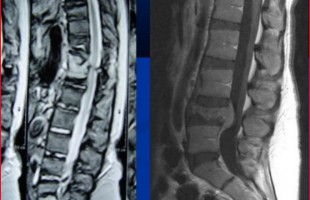

Η Μα. Φο. 26 ετών προ δεκαετίας υποβλήθηκε (αλλαχού) σε χειρουργική επέμβαση στη θωρακο-οσφυική περιοχή της σπονδυλικής στήλης (Σ.Σ.). Η επέμβαση εγένετο προκειμένου να αφαιρεθεί καλοήθης νεοπλασματική εξεργασία (επενδύμωμα) η οποία της είχε προκαλέσει σφιγκτηριακές και νευρολογικές διαταραχές στα κάτω άκρα. Προκειμένου να γίνει εξαίρεση της νεοπλασματικής βλάβης, πραγματοποιήθηκε ευρεία αφαίρεση οπίσθιων στηρικτικών στοιχείων τωνRead more →